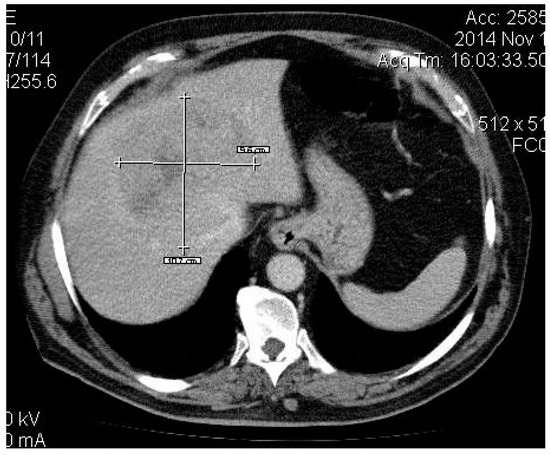

2. Case Presentation